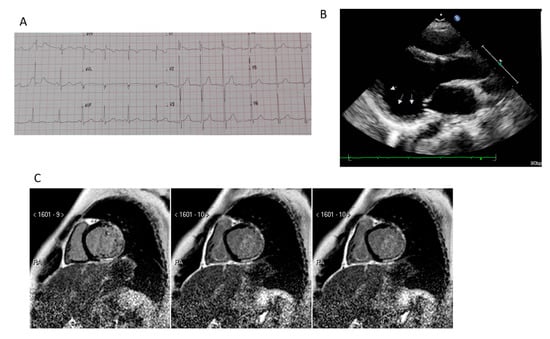

5.2. Cardiac Magnetic Resonance